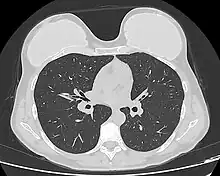

Implant rupture visualized by breast computed tomography

Because a breast implant is a Class III medical device of limited product-life, the principal rupture-rate factors are its age and design; nonetheless, a breast implant device can retain its mechanical integrity for decades in a woman's body.[43] When a saline breast implant ruptures, leaks, and empties, it quickly deflates, and thus can be readily explanted (surgically removed). In some cases, saline implant rupture can result in an infection due to bacteria or mold that had been within the implant, though this is uncommon.[44] The follow-up report, Natrelle Saline-filled Breast Implants: a Prospective 10-year Study (2009) indicated rupture-deflation rates of 3–5 per cent at 3-years post-implantation, and 7–10 per cent rupture-deflation rates at 10-years post-implantation.[45] In a study of his 4761 augmentation mammaplasty patients, Eisenberg reported that overfilling saline breast implants 10-13% significantly reduced the rupture-deflation rate to 1.83% at 8-years post-implantation.[46]